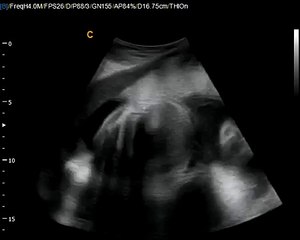

12 Weeks Pregnant Gender Determination Ultrasound

85 chance its a girl - determined at the end where the cursor is pointing\rbr\rbr*confirmed 100 at 20-week ultrasound